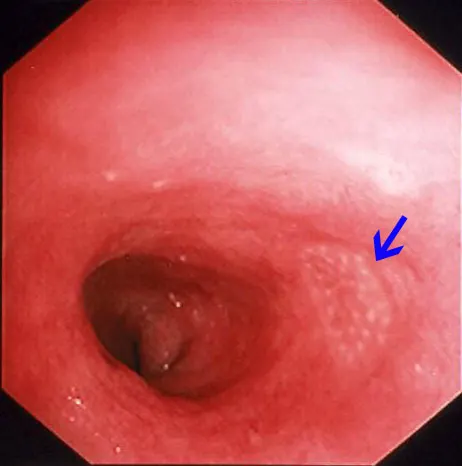

Compared to other alimentary tract organs, the duodenal mucosa has a more granular texture, due to its prominent villous architecture. Duodenal and jejunal mucosa color varies from pale pink to tan in animals having recent biliary secretion. Submucosal lymphoid aggregates appear as oval, slightly depressed mucosal structures present along the descending duodenum (in dogs) and should not be interpreted as mucosal lesions. Other normal mucosal structures include the major duodenal papillae (present in the dog and cat) and minor duodenal papillae (present only in the dog) (Figure 1).

Endoscopic appearance of the normal proximal duodenum in a dog. A lymphoid aggregate (A, arrow) is clearly visible along the lateral mucosal wall. This structure should not be biopsied as such samples confound histologic determination of lymphocytic enteritis. The major duodenal papilla (B, arrow) and a linear mucosal erosion caused by passage of the endoscope through the cranial duodenal flexure are shown in B.